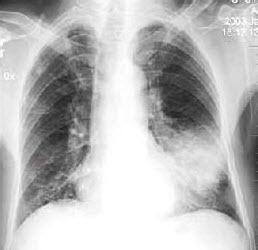

拍了个胸部X线片,在胸片上表现为:左下肺似肺炎的团块样病灶,一块一块的分布着(医学上叫肺部阴影),看上去十分酷似肺炎的X线表现,病灶阴影的形状多样不规则。

肺结核!?高度怀疑!虽然没有咳嗽咳痰、咯血、胸痛、潮热盗汗等肺结核的典型症状,但是他外出打工,生活艰苦,身体免疫力明显下降,易受到结核菌的感染,并且已经用了这么多高档的抗生素治疗肺炎,治疗无效,再不能考虑肺炎了。